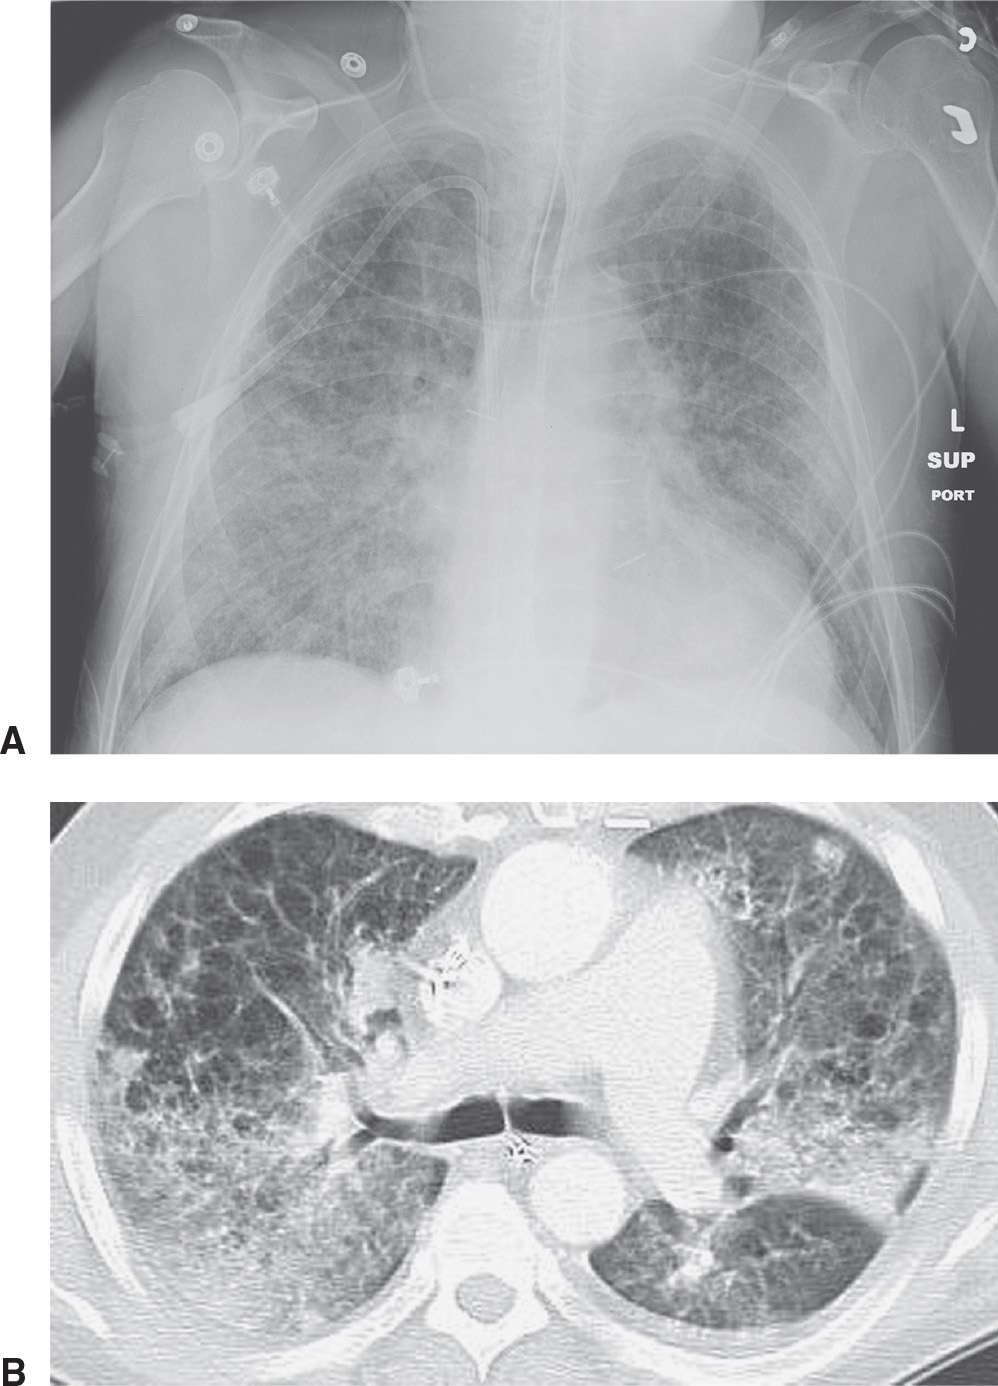

Chest X Ray Findings Interstitial Lung Disease . The causes of ild include occupational and environmental exposures as well as genetic, idiopathic, and connective tissue disorders. 3 4 some forms of i. Patients with interstitial lung disease often present with breathlessness, chronic cough, inspiratory crackles on auscultation, and abnormal spirometry. 1 2 over 200 different types of disease can cause thickening of the pulmonary interstitium, with the common final pathway for many of these being fibrosis (figs 1 and 2) ⇓ ⇓. Until today, computed tomography (ct) is the most important and valuable radiological modality to detect, analyze, and diagnose diffuse interstitial. Interstitial lung abnormalities (ilas) are common incidental findings at ct, which progress over 5 years in more than 50% of individuals, and are associated with worsened clinical outcomes, including respiratory symptoms, exercise capacity, lung function, and mortality. 1 recognition of key imaging features and patterns in addition to disease distribution in the lungs are vital for an accurate diagnosis of ild by radiologists.

Until today, computed tomography (ct) is the most important and valuable radiological modality to detect, analyze, and diagnose diffuse interstitial. The causes of ild include occupational and environmental exposures as well as genetic, idiopathic, and connective tissue disorders. 3 4 some forms of i. 1 2 over 200 different types of disease can cause thickening of the pulmonary interstitium, with the common final pathway for many of these being fibrosis (figs 1 and 2) ⇓ ⇓. Interstitial lung abnormalities (ilas) are common incidental findings at ct, which progress over 5 years in more than 50% of individuals, and are associated with worsened clinical outcomes, including respiratory symptoms, exercise capacity, lung function, and mortality. 1 recognition of key imaging features and patterns in addition to disease distribution in the lungs are vital for an accurate diagnosis of ild by radiologists. Patients with interstitial lung disease often present with breathlessness, chronic cough, inspiratory crackles on auscultation, and abnormal spirometry.